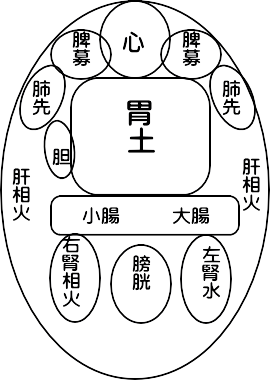

| HOME > 学習ノート> >お腹のみかた、触れ方② 腹診は先人たちのご苦労されて残されたものから、多くを学ぶことができます。 たにぐち書店の難経からお腹の経絡図をお借りして載せています。 ツボも細かく書かれていますが、お腹にはすべての経絡が関わっています。 肺経は経絡図を見ますと、表面上では胸部の一部と腕だけだと思われますが、決してそうではなく腹部の中に 入って働いていることが右の図をご覧頂くとお判り頂けるかと存じます。   また、お腹のみかたも、鍼道秘訣集、夢分の描かれたものや増永静人先生の腹部スジ反応部位をご覧頂くと、 人により観方、感じ方が異なっていることが分かるかと思います。 ではどちらを信じて学べば良いのでしょうか。 どちらの方もこの道の大家でいらっしゃいますから迷うでしょう。 答えですが、まず、どちらも覚え、頭の片隅に入れておきますが、最終的には幾度も施術をしながら自分の感覚 を信じ、答えを出すことです。 鍼道秘訣集 夢分

増永静人 経絡図